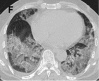

Figure 3a.

A-C. Non-contrast chest CT images of a 56 year old man with severe COVID-19 pneumonia. CT scans show multiple ground-glass opacities in multiple lung segments, the CT-SS is 28. D-F. Non-contrast chest CT images of a 69 year old man with severe COVID-19 …

Figure 3b.